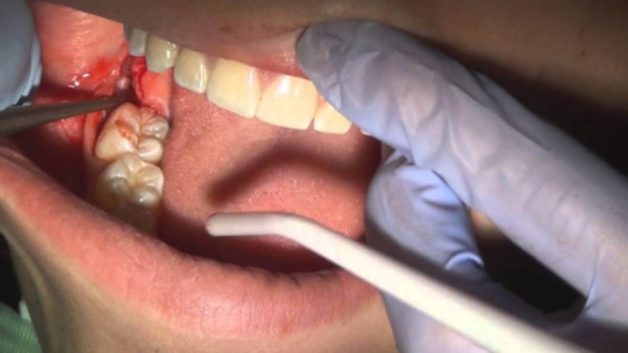

Piezotome là phương pháp nhổ răng khôn hiện đại, an toàn và nhẹ nhàng nhất hiện nay

Nha Khoa Thu Cúc TCI hiện dang là một trong những địa chỉ hàng đầu trong chăm sóc sức khỏe răng miệng với cơ sở vật chất khang trang, sạch sẽ, thiết bị hiện đại, tân tiến cùng đội ngũ nha sĩ giỏi chuyên môn, dày kinh nghiệm, tay nghề cao. Đặc biệt, Nha Khoa Thu Cúc TCI đang áp dụng phương pháp nhổ răng khôn mọc lệch bằng phương pháp Piezotome hiện đại nhất hiện nay. Sử dụng sóng siêu âm, Piezotome sẽ loại bỏ hoàn toàn mọi chiếc răng cứng đầu và giảm thiểu tổn thương tối đa cho các khu vực xung quanh trong quá trình nhổ răng. Êm ái, an toàn, nhanh chóng, nhanh hồi phục vết thương – Piezotome là phương pháp nhổ răng vượt trội hơn hẳn phương pháp truyền thống, nhất là với những ca nhổ khó.